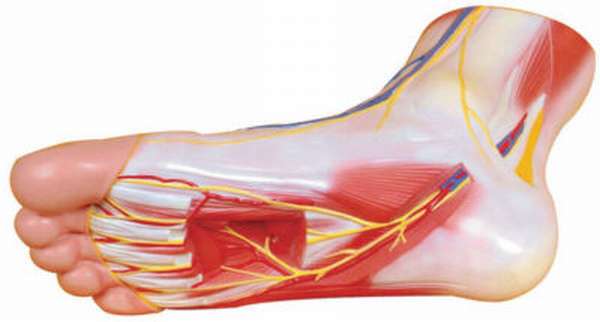

Анатомия голеностопа: Сухожилия и их строение